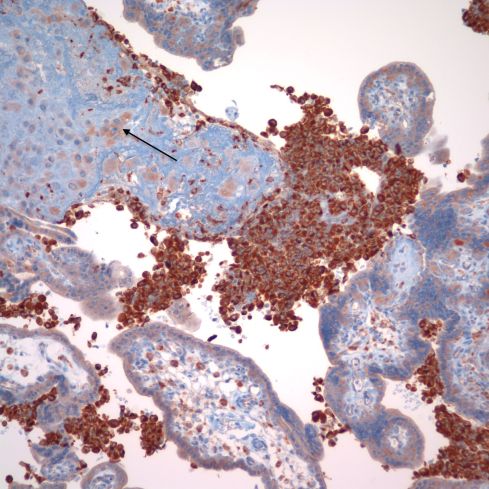

Recently I received an email from Dr. Peilin Zhang with some publications he had written about acute atherosis18(http://dx.doi.org/10.1101/293027.). He demonstrated cytokeratin (AE1/AE3) and , CD56 staining in the foam cells in acute atherosis. He argued that the assumption that the lipid cells in acute atherosis were macrophages was based on morphologic analogy with atheromas in arteriosclerosis and by CD68 staining, and is wrong. I have to admit that CD68 is not specific for macrophages, and in fact I had often seen that is was immuno-positive in cytotrophoblast cells (Fig 34).

Fig 34: This image of placenta demonstrates massive chronic intervillositis with the many monocytic cells stained deeply dark brown for the antigen CD68. The arrow demonstrates the paler, but still positive for CD68 cytotrophoblastic cells embedded in the surrounding fibrinoid. (CD68, 20x)